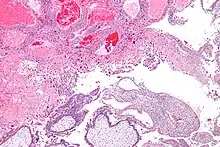

| Micrograph of intermediate trophoblast, decidua and a hydatidiform mole (bottom of image). H&E stain. | |